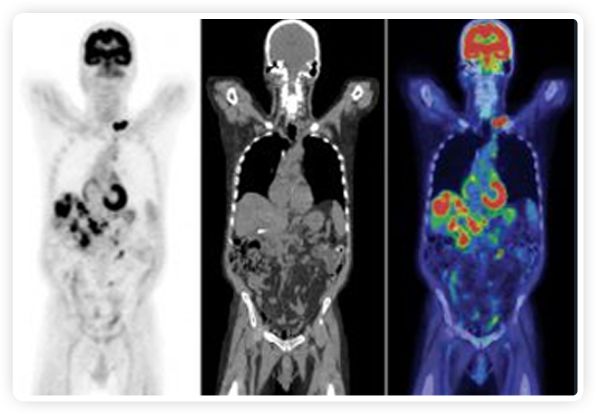

正電子發(fā)射斷層掃描(PET)是癌癥檢測中已建立的成像標(biāo)準(zhǔn),與其他成像方式相比,PET能提供高靈敏度和特異性的圖像。

到目前為止,放射腫瘤學(xué)中(使用的圖像主要是結(jié)構(gòu)性的,而PET圖像可以提供生物學(xué)信息。通過使用注射示蹤劑,例如18-FDG,PET可以描繪腫瘤的代謝活性,使其“點亮”。(FDG是用于可視化癌癥代謝的最廣泛使用的示蹤劑。與正常組織相比,腫瘤細胞保留更高水平的FDG。)不同的PET示蹤劑可以識別腫瘤的不同生物學(xué)特征,例如特定生物標(biāo)志物抗原(例如,PSMA)或甚至探測免疫系統(tǒng)本身(例如,PDL1表達或活化的T細胞)。

RefleXion將PET成像與立體定向放射治療相結(jié)合。在注射示蹤劑后,RefleXion的技術(shù)基于示蹤劑信號實時地在一個或多個目標(biāo)上引導(dǎo)治療性X射線。使用這種專有方法,RefleXion的平臺有可能比現(xiàn)有系統(tǒng)向癌癥病變提供更高劑量的輻射,并改善周圍健康組織的保護。